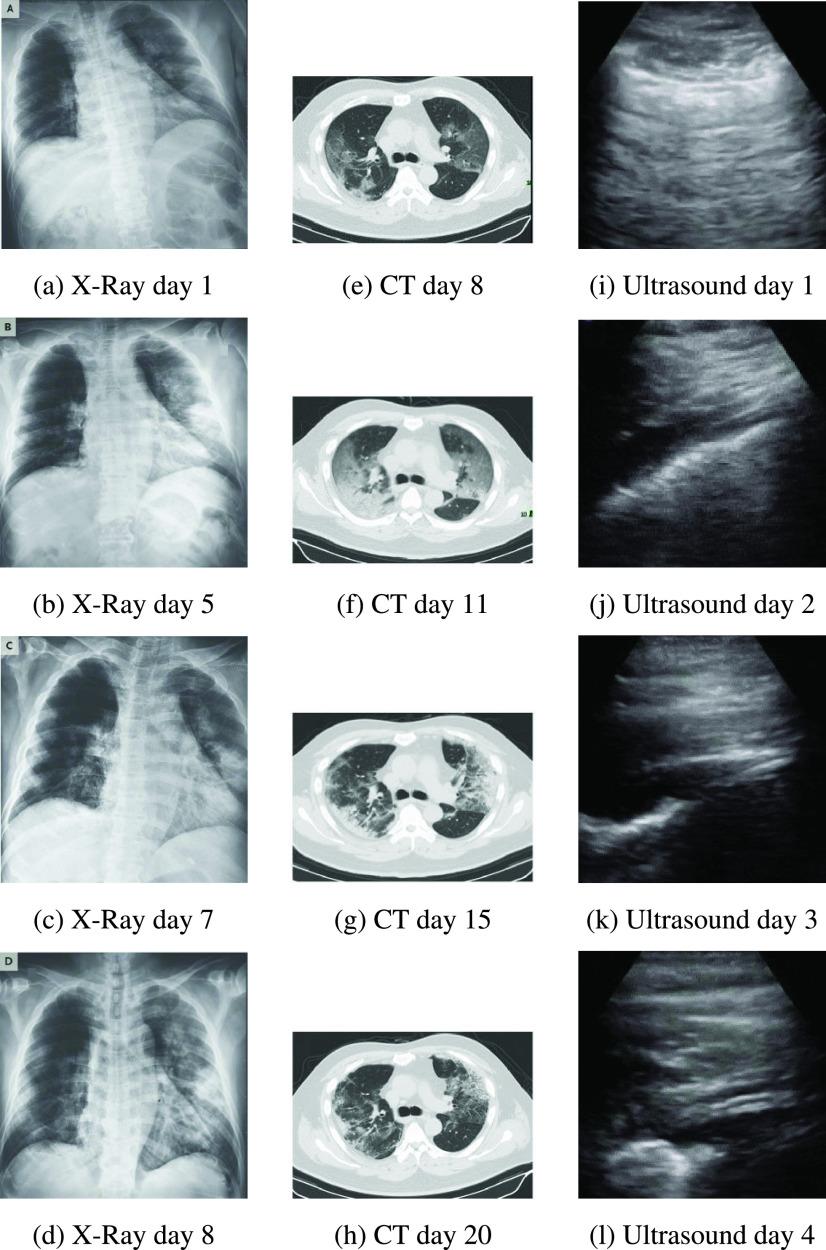

Detecting COVID-19 early may help in devising an appropriate treatment plan and disease containment decisions. In this study, we demonstrate how transfer learning from deep learning models can be used to perform COVID-19 detection using images from three most commonly used medical imaging modes X-Ray, Ultrasound, and CT scan. The aim is to provide over-stressed medical professionals a second pair of eyes through intelligent deep learning image classification models. We identify a suitable (CNN) model through initial comparative study of several popular CNN models. We then optimize the selected VGG19 model for the image modalities to show how the models can be used for the highly scarce and challenging COVID-19 datasets. We highlight the challenges (including dataset size and quality) in utilizing current publicly available COVID-19 datasets for developing useful deep learning models and how it adversely impacts the trainability of complex models. We also propose an image pre-processing stage to create a trustworthy image dataset for developing and testing the deep learning models. The new approach is aimed to reduce unwanted noise from the images so that deep learning models can focus on detecting diseases with specific features from them. Our results indicate that Ultrasound images provide superior detection accuracy compared to X-Ray and CT scans. The experimental results highlight that with limited data, most of the deeper networks struggle to train well and provides less consistency over the three imaging modes we are using. The selected VGG19 model, which is then extensively tuned with appropriate parameters, performs in considerable levels of COVID-19 detection against pneumonia or normal for all three lung image modes with the precision of up to 86% for X-Ray, 100% for Ultrasound and 84% for CT scans.

早期检测新冠病毒有助于制定合适的治疗方案和疾病防控决策。在本研究中,我们展示了如何利用深度学习模型的迁移学习,通过三种最常用的医学成像模式(X光、超声和CT扫描)的图像来进行新冠病毒检测。目的是通过智能深度学习图像分类模型为不堪重负的医学专业人员提供“第二双眼睛”。我们通过对几种流行的卷积神经网络(CNN)模型进行初步比较研究,确定了一个合适的模型。然后,我们针对图像模态对选定的VGG19模型进行优化,以展示这些模型如何用于高度稀缺且具有挑战性的新冠病毒数据集。我们强调了利用当前公开可用的新冠病毒数据集开发有用的深度学习模型时所面临的挑战(包括数据集的大小和质量),以及这如何对复杂模型的可训练性产生不利影响。我们还提出了一个图像预处理阶段,以创建一个可靠的图像数据集来开发和测试深度学习模型。新方法旨在减少图像中的不必要噪声,以便深度学习模型能够专注于从图像中检测具有特定特征的疾病。我们的结果表明,与X光和CT扫描相比,超声图像具有更高的检测准确率。实验结果突出表明,在数据有限的情况下,大多数更深层次的网络难以良好训练,并且在我们使用的三种成像模式下一致性较差。选定的VGG19模型经过适当参数的广泛调整后,在针对所有三种肺部图像模式检测新冠病毒与肺炎或正常情况时表现出色,X光检测精度高达86%,超声检测精度达100%,CT扫描检测精度达84%。